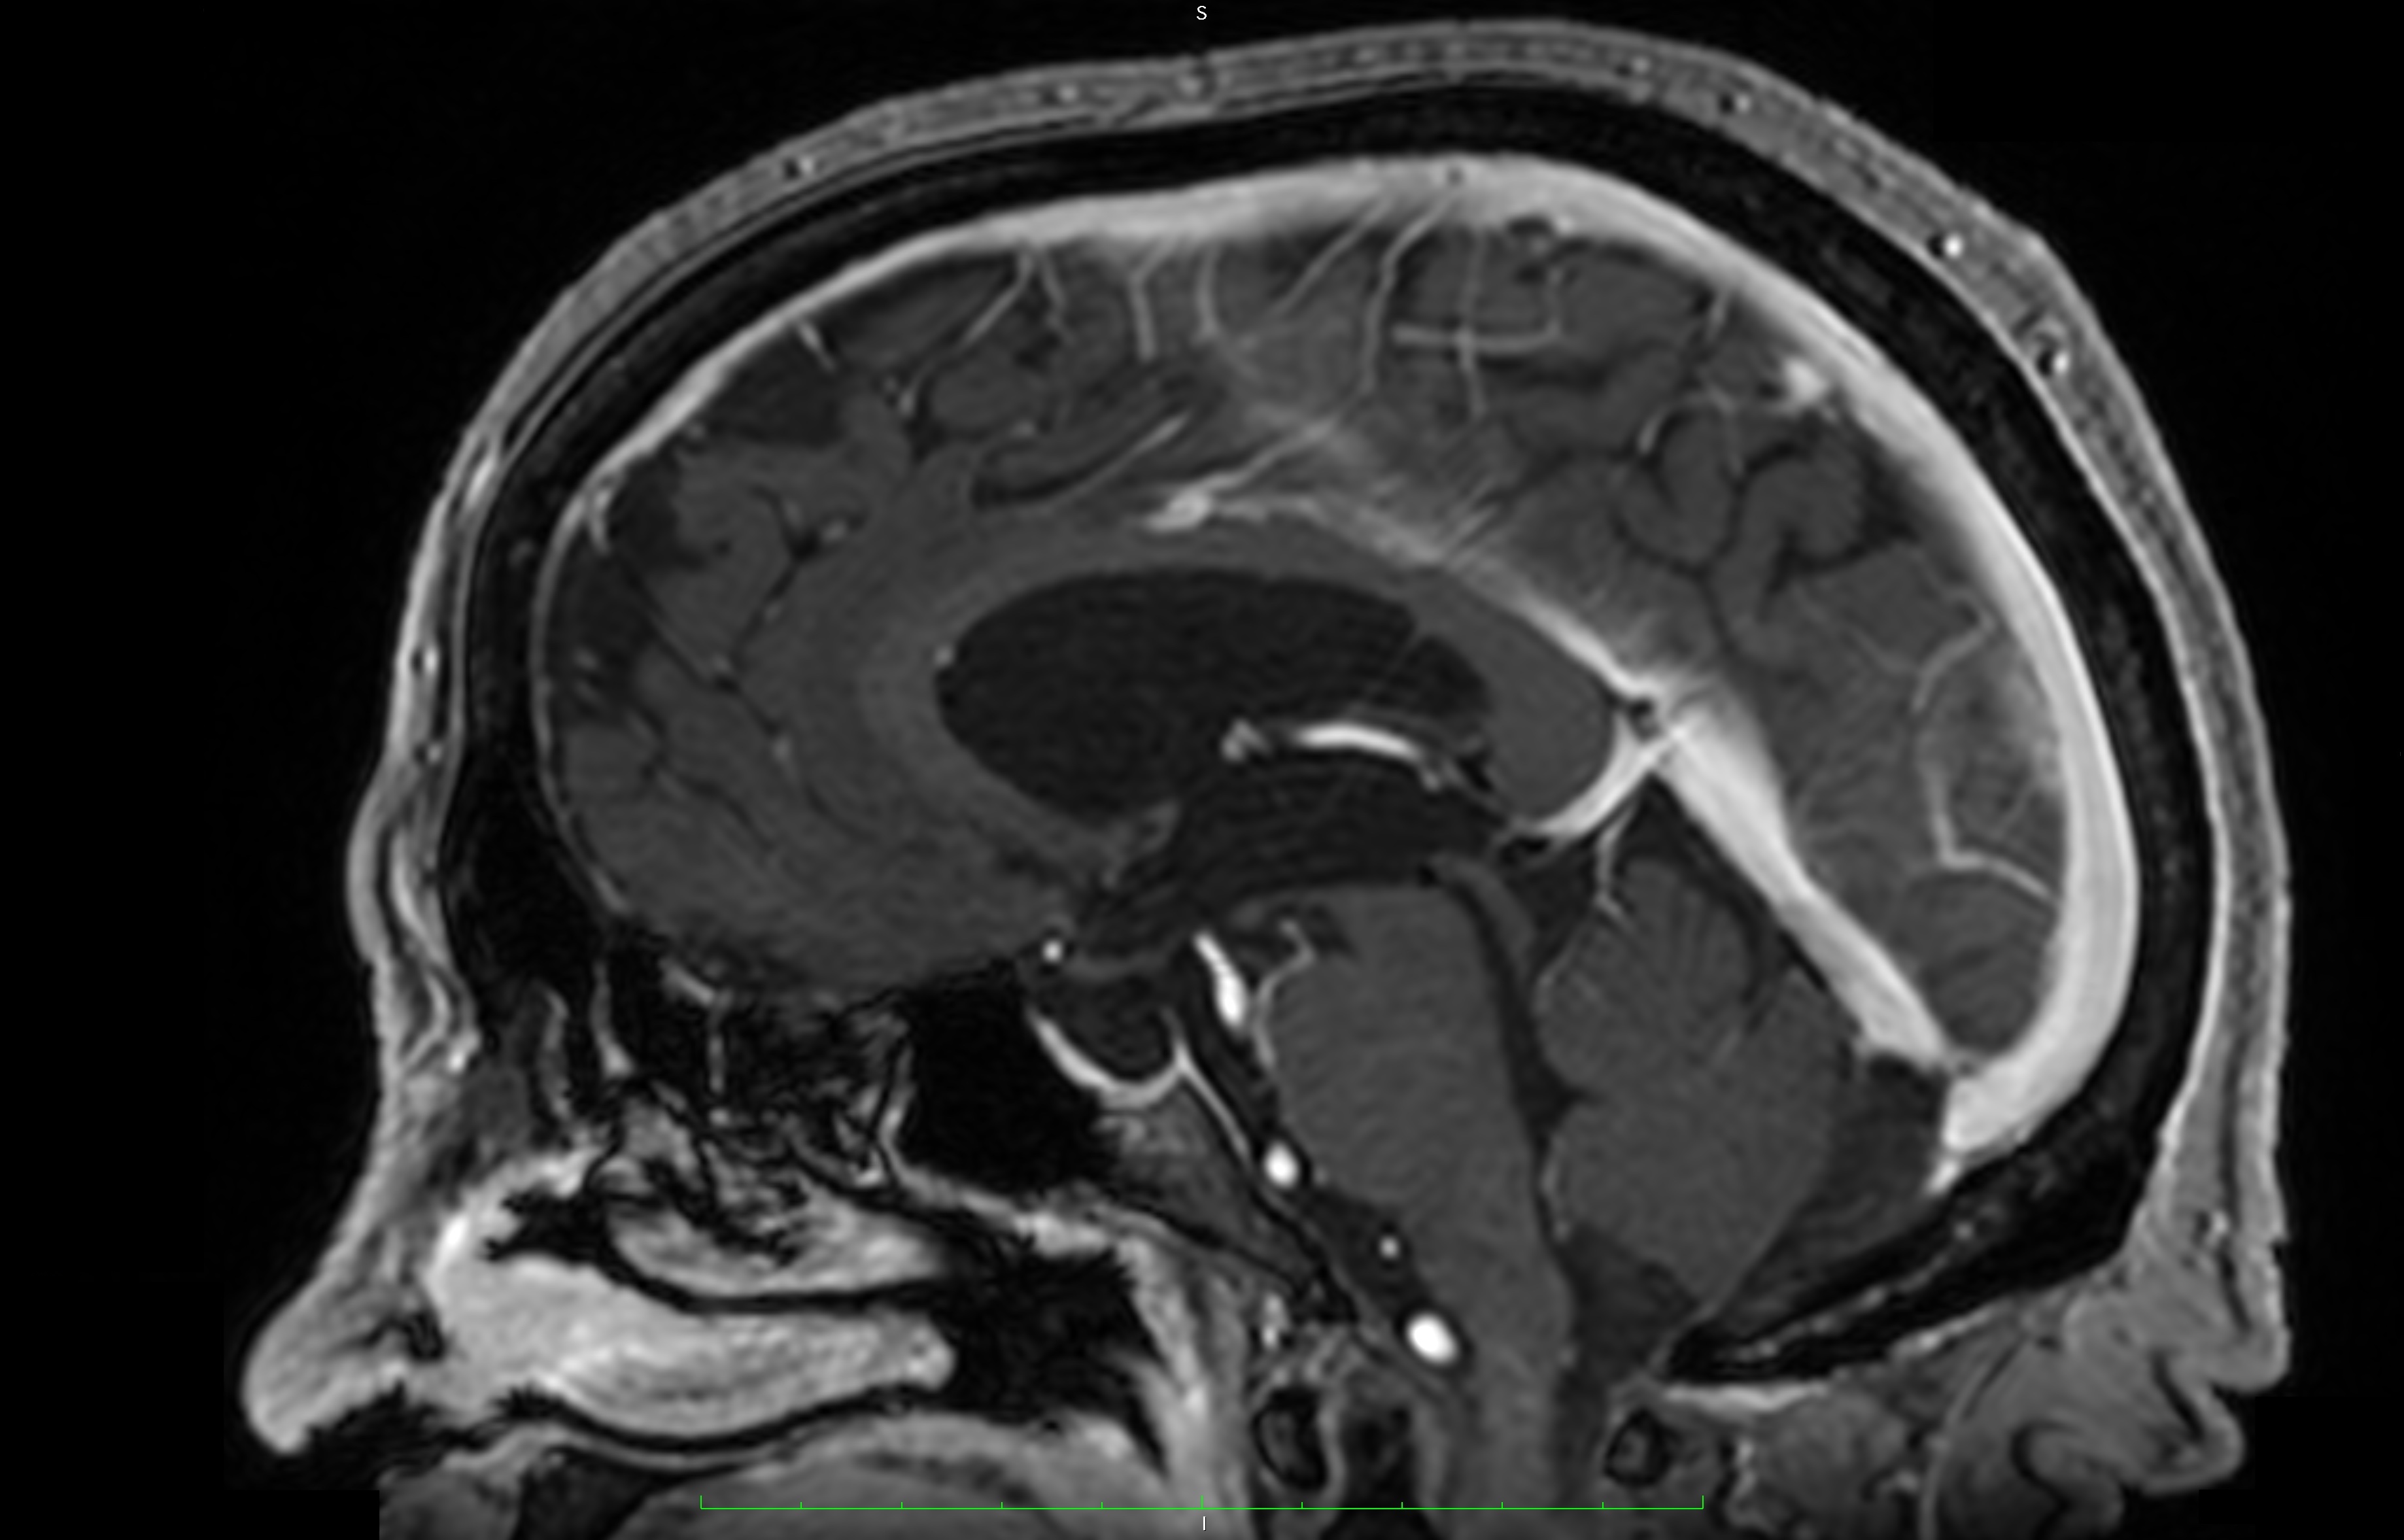

Pathologies of the pineal gland region are frequently encountered in daily neurosurgical practice. It is important to remember that, besides usually asymptomatic pineal gland cysts, neoplasms of a different origin may also occur in this region. The rarity of the most dangerous lesions – pineal gland apoplexy and pineal tumors – might cause problems with proper diagnosis and treatment. Their occurrence is commonly associated with symptomatic hydrocephalus caused by aqueductal stenosis. Currently, in such cases, endoscopic procedures, including endoscopic third ventriculostomy (ETV), are commonly and widely chosen as treatment options. Endoscopic procedures not only enable decompression of hydrocephalus but also further diagnosis of its cause. Herein, we present 3 case reports of endoscopic treatment with ETV performed in patients with hydrocephalus related to pineal region pathologies.